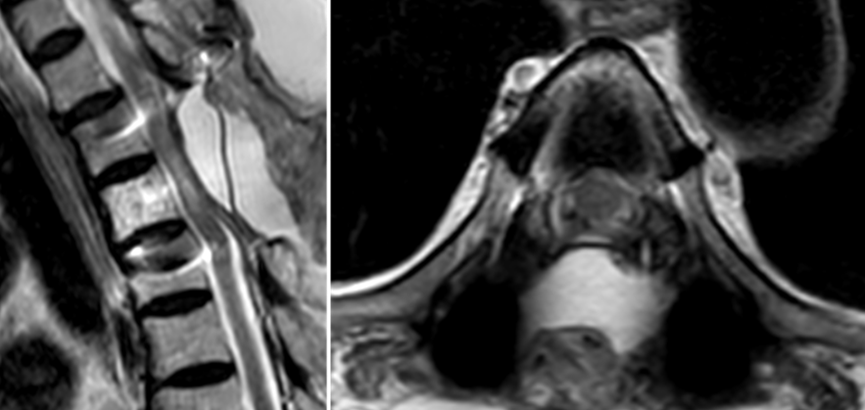

术前胸椎MRI可见椎管内巨大肿瘤,脊髓受压呈线型

术后3天复查胸椎MRI示肿瘤完整切除,脊髓复张良好